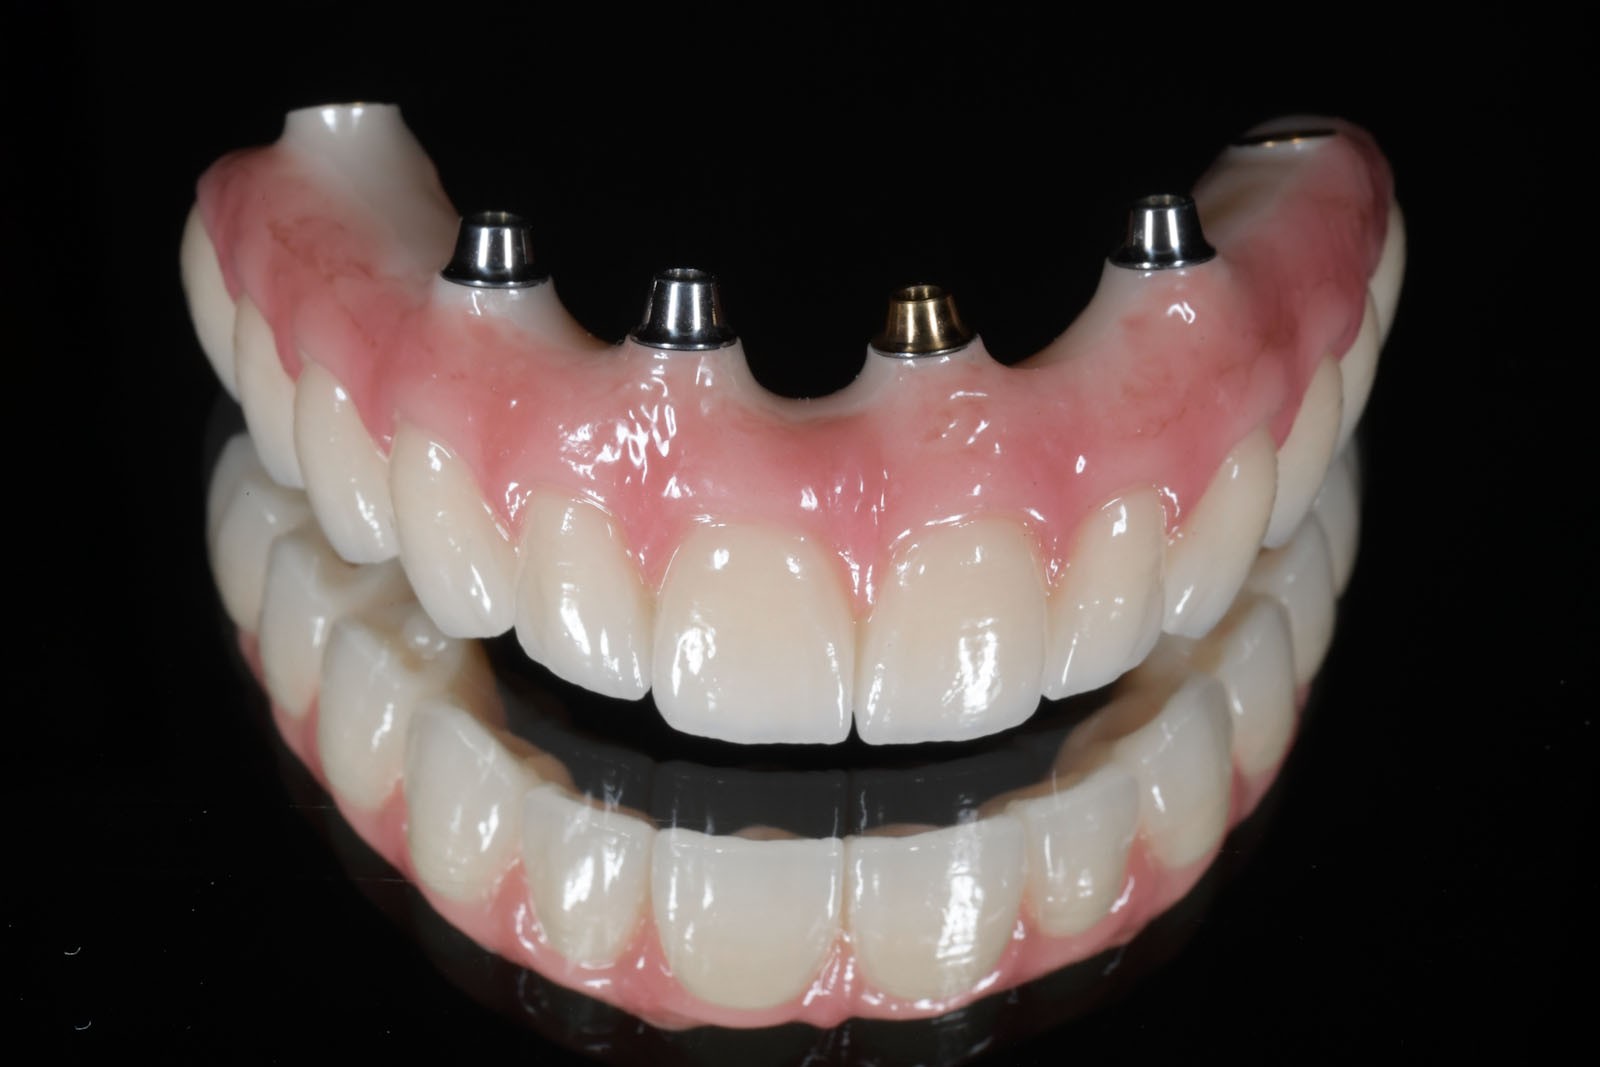

Komfortową alternatywą dla mostu jest rehabilitacja implanto-protetyczna, zarówno w przypadku braku pojedynczego, jak i większej liczby zębów. Implantacja wskazana jest w szczególności, gdy zęby sąsiadujące z luką są zdrowe, nie leczone kanałowo, a podłoże kostne spełnia warunki dla implantacji. Pozwala to uniknąć szlifowania zębów filarowych stojących obok luki, a przyszła konstrukcja protetyczna najczęściej nie uwzględnia przęsła mostu, które może sprawiać trudności w utrzymaniu higieny jamy ustnej. Korony i mosty wsparte na implantach przenoszą siły powstające w procesie żucia przez osie implantów wszczepionych w kość. Tworzy to układ działania sił najbardziej zbliżony do fizjologicznych warunków jamy ustnej z uzębieniem. Jest on optymalny dla zdrowia i zachowania tkanki kostnej. W ten sposób przenoszona siła powoduje wzmocnienie kości, nie zaś jej resorpcję, czyli zanik.

Ciągle powszechnie stosowanym uzupełnieniem protetycznym jest całkowita proteza osiadająca. Zaletami tego rozwiązania są ogólna dostępność, prostota i krótki czas wykonania. Często o wyborze protezy całkowitej decyduje niski jej koszt oraz zadowalający efekt estetyczny w krótkim czasie. Wadę stanowi mały komfort użytkowania oraz stale zanikające podłoże kostne pod protezą, powodowane uciskiem. Proteza tylko w niewielkim stopniu odtwarza utraconą funkcję żucia, a ze względu na pokrycie podniebienia przez płytę protezy, upośledzone zostaje odczuwanie smaku i temperatury spożywanych potraw. W zależności od stanu kości szczęk i żuchwy rozwiązaniem alternatywnym dla pacjenta są uzupełnienia protetyczne wsparte na implantach.

W związku z ich użytkowaniem skala komfortu dla pacjenta zależy od tego, czy są to ruchome protezy Overdenture oparte jedynie na implantach, które poprawiają stabilizację protez zębowych, czy też na stałe mocowane na wszczepach mosty. W ślad za wyborem rodzaju mocowania protez idzie jakość odbudowy protetycznej. Protezy Overdenture są wykonane z materiału kompozytowego lub akrylu, natomiast mosty są wykonane z ceramiki.